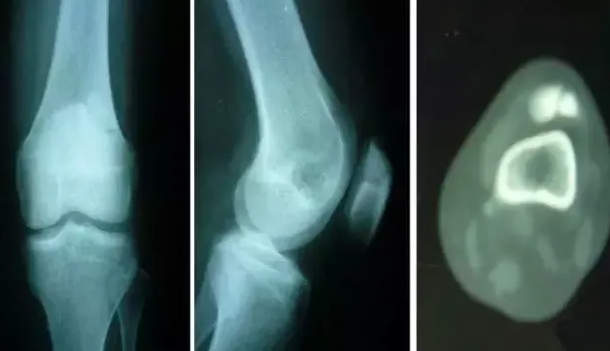

엑스레이나 CT 또는 MRI 촬영등으로 활액낭염의 진단을 받을 수 있으며 기본적으로 증상을 악화시킬 수 있는 동작이나 활동을 피하는것이 가장 중요합니다. 또한 주기적인 얼음찜질을 통해 붓기를 가라앉히고 통증을 완화시킬 수 있으며 병원의 처방으로 항염증제를 복용하면 통증과 염증을 줄이는데 도움이 됩니다.